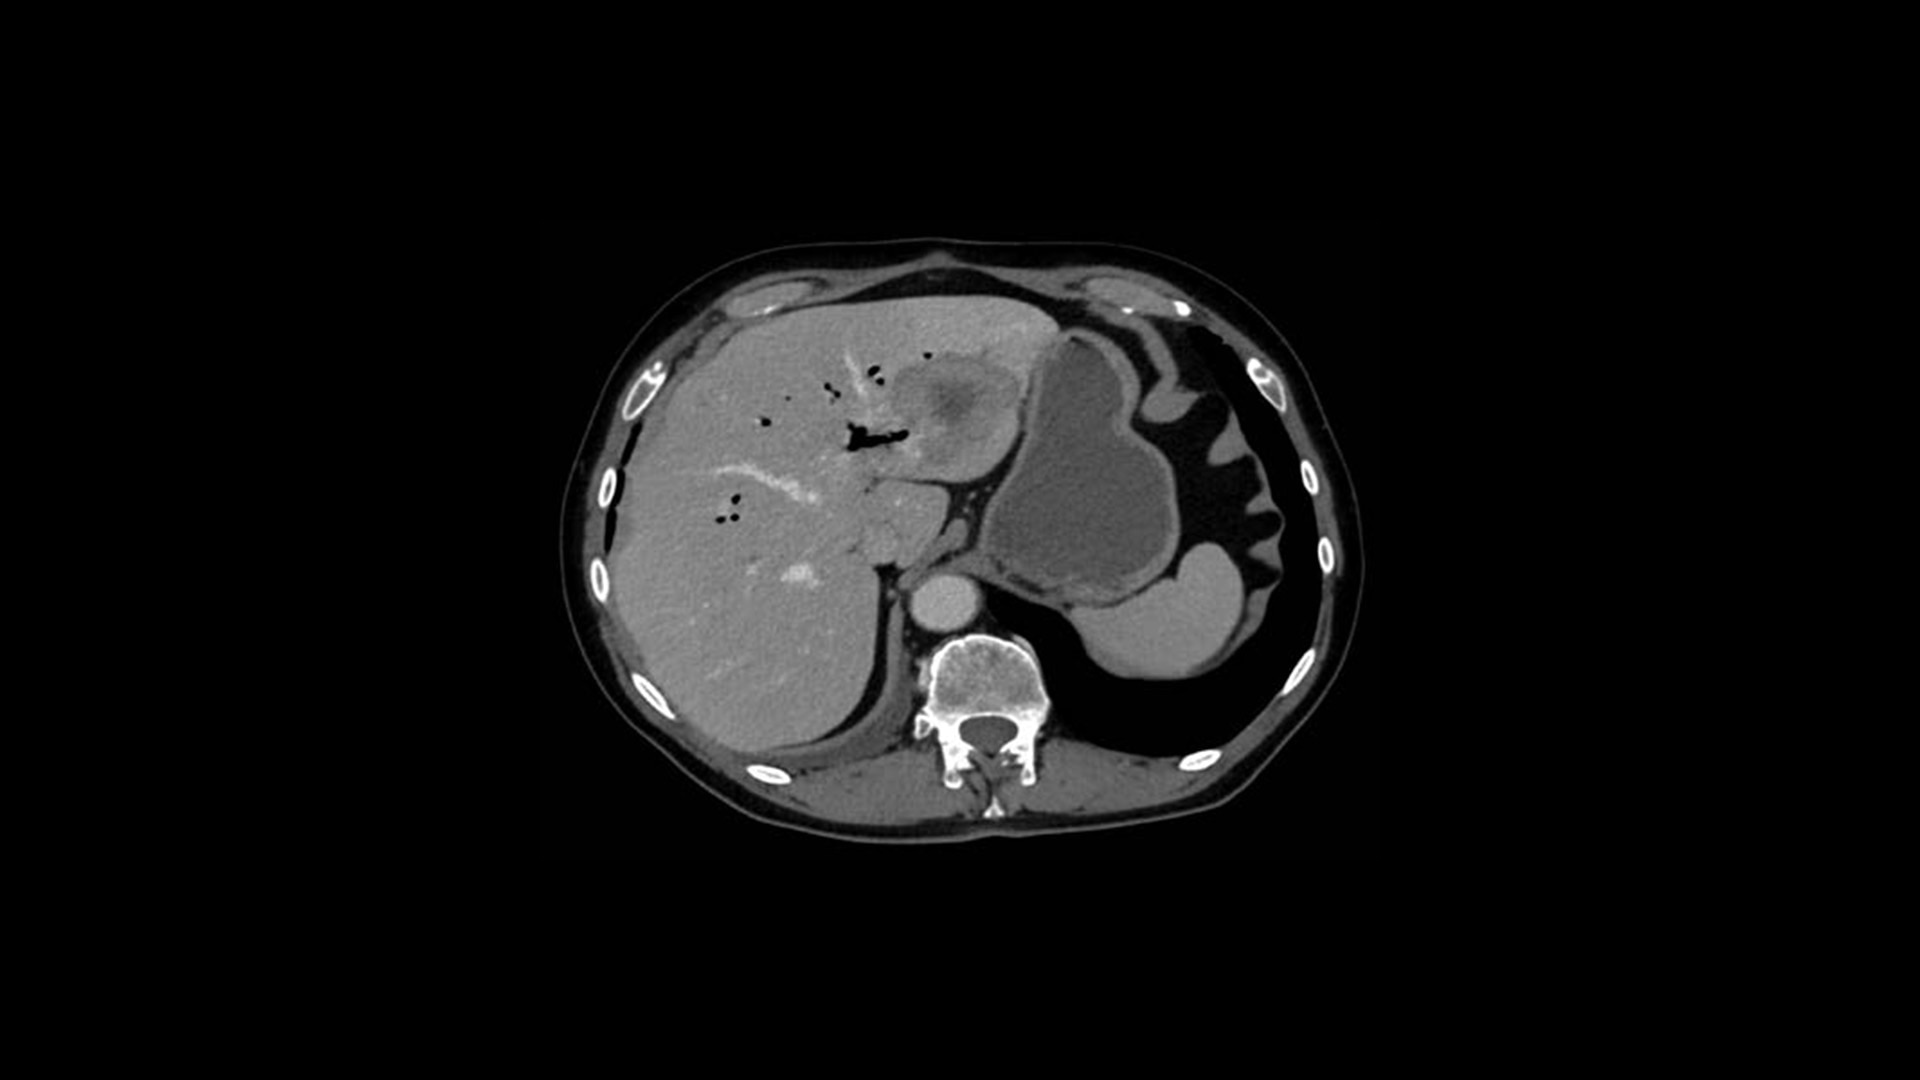

True Enhance DL

Designed to enhance what matters

True Enhance DL is a deep learning-based processing method intended for contrast enhancement of single energy images. True Enhance DL uses a dedicated Deep Neural Network (DNN) trained to estimate monochromatic, 50 keV GSI images from single-energy X-ray. This technology brings four deep learning models that the user can choose depending on different contrast enhancement phases by clinical tasks.